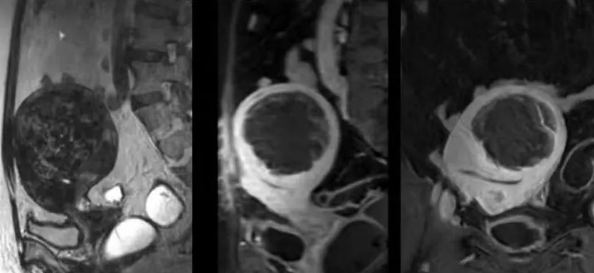

陳寶瑩主任首先給祝女士進(jìn)行了詳細(xì)的盆腔磁共振評(píng)估,發(fā)現(xiàn)子宮肌瘤比較大,直徑七公分,類型和位置都適合做磁波刀治療。陳寶瑩主任立即為她制定了個(gè)性化治療方案,并為她完成幾項(xiàng)術(shù)前檢查。

治療當(dāng)天,為緩解祝女士的緊張心情,陳寶瑩主任和她進(jìn)行了充分溝通。術(shù)前準(zhǔn)備就緒后,治療正式開(kāi)始了。治療過(guò)程中,患者全程清醒,可以及時(shí)反饋治療感受。醫(yī)生也即時(shí)調(diào)整,確保整個(gè)治療安全有效,兩小時(shí)后治療順利結(jié)束,患者體驗(yàn)度好。即時(shí)評(píng)估發(fā)現(xiàn)7公分的子宮肌瘤被消融掉80%,達(dá)到了預(yù)期目標(biāo)。祝女士觀察一個(gè)小時(shí)后,沒(méi)有什么不舒服即回家了。